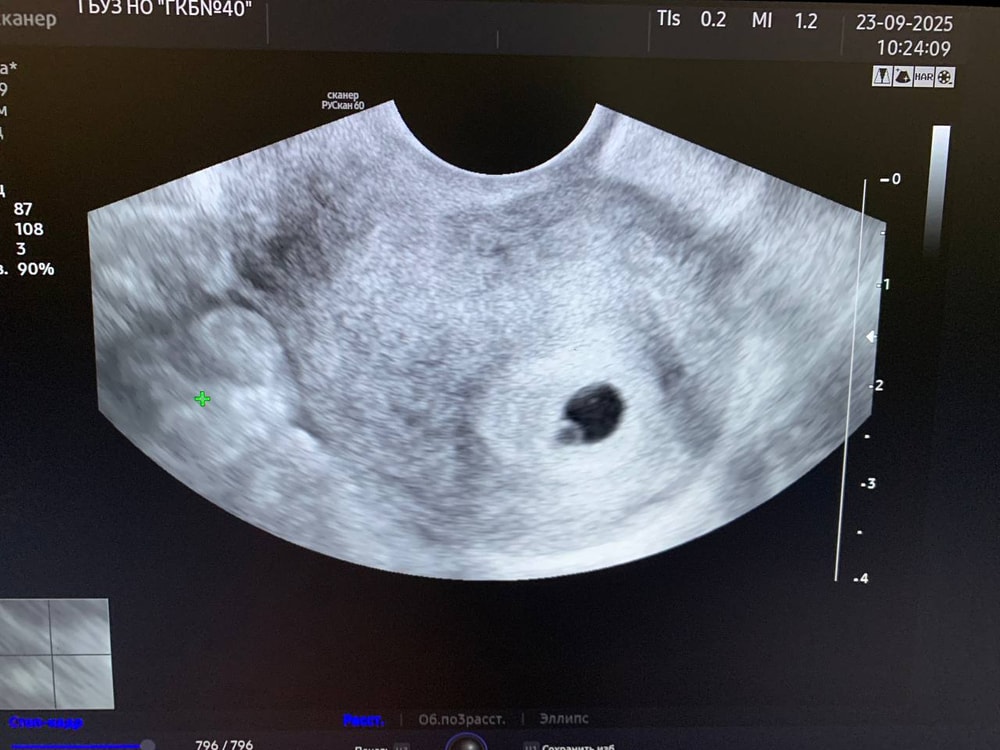

Была сегодня на УЗИ для подтверждения беременности. Последние месячные были 8.08.25г., т.е. по ним срок 6 недель. На УЗИ еще не увидели эмбриона, сказали что вроде срок меньше 6 недель. Точную дату зачатия не знаю, поэтому срок сама не могу уточнить, но цикл у меня 31-34 дня.

Посмотрите, пожалуйста, УЗИ. Может ли из такого все таки вырасти эмбрион?

По последним М у вас срок уже 6.4, у меня в этот раз в 6.5 уже нашли сердечко

А плодное яйцо? Какие размеры? ЖМ?